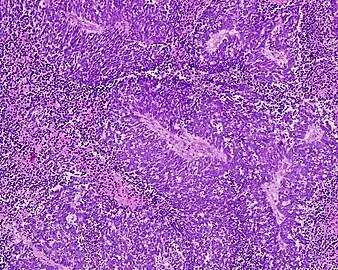

Small-cell carcinoma is an undifferentiated neoplasm composed of primitive-appearing cells. As the name implies, the cells in small-cell carcinomas are smaller than normal cells, and barely have room for any cytoplasm. Some researchers identify this as a failure in the mechanism that controls the size of the cells.[43]